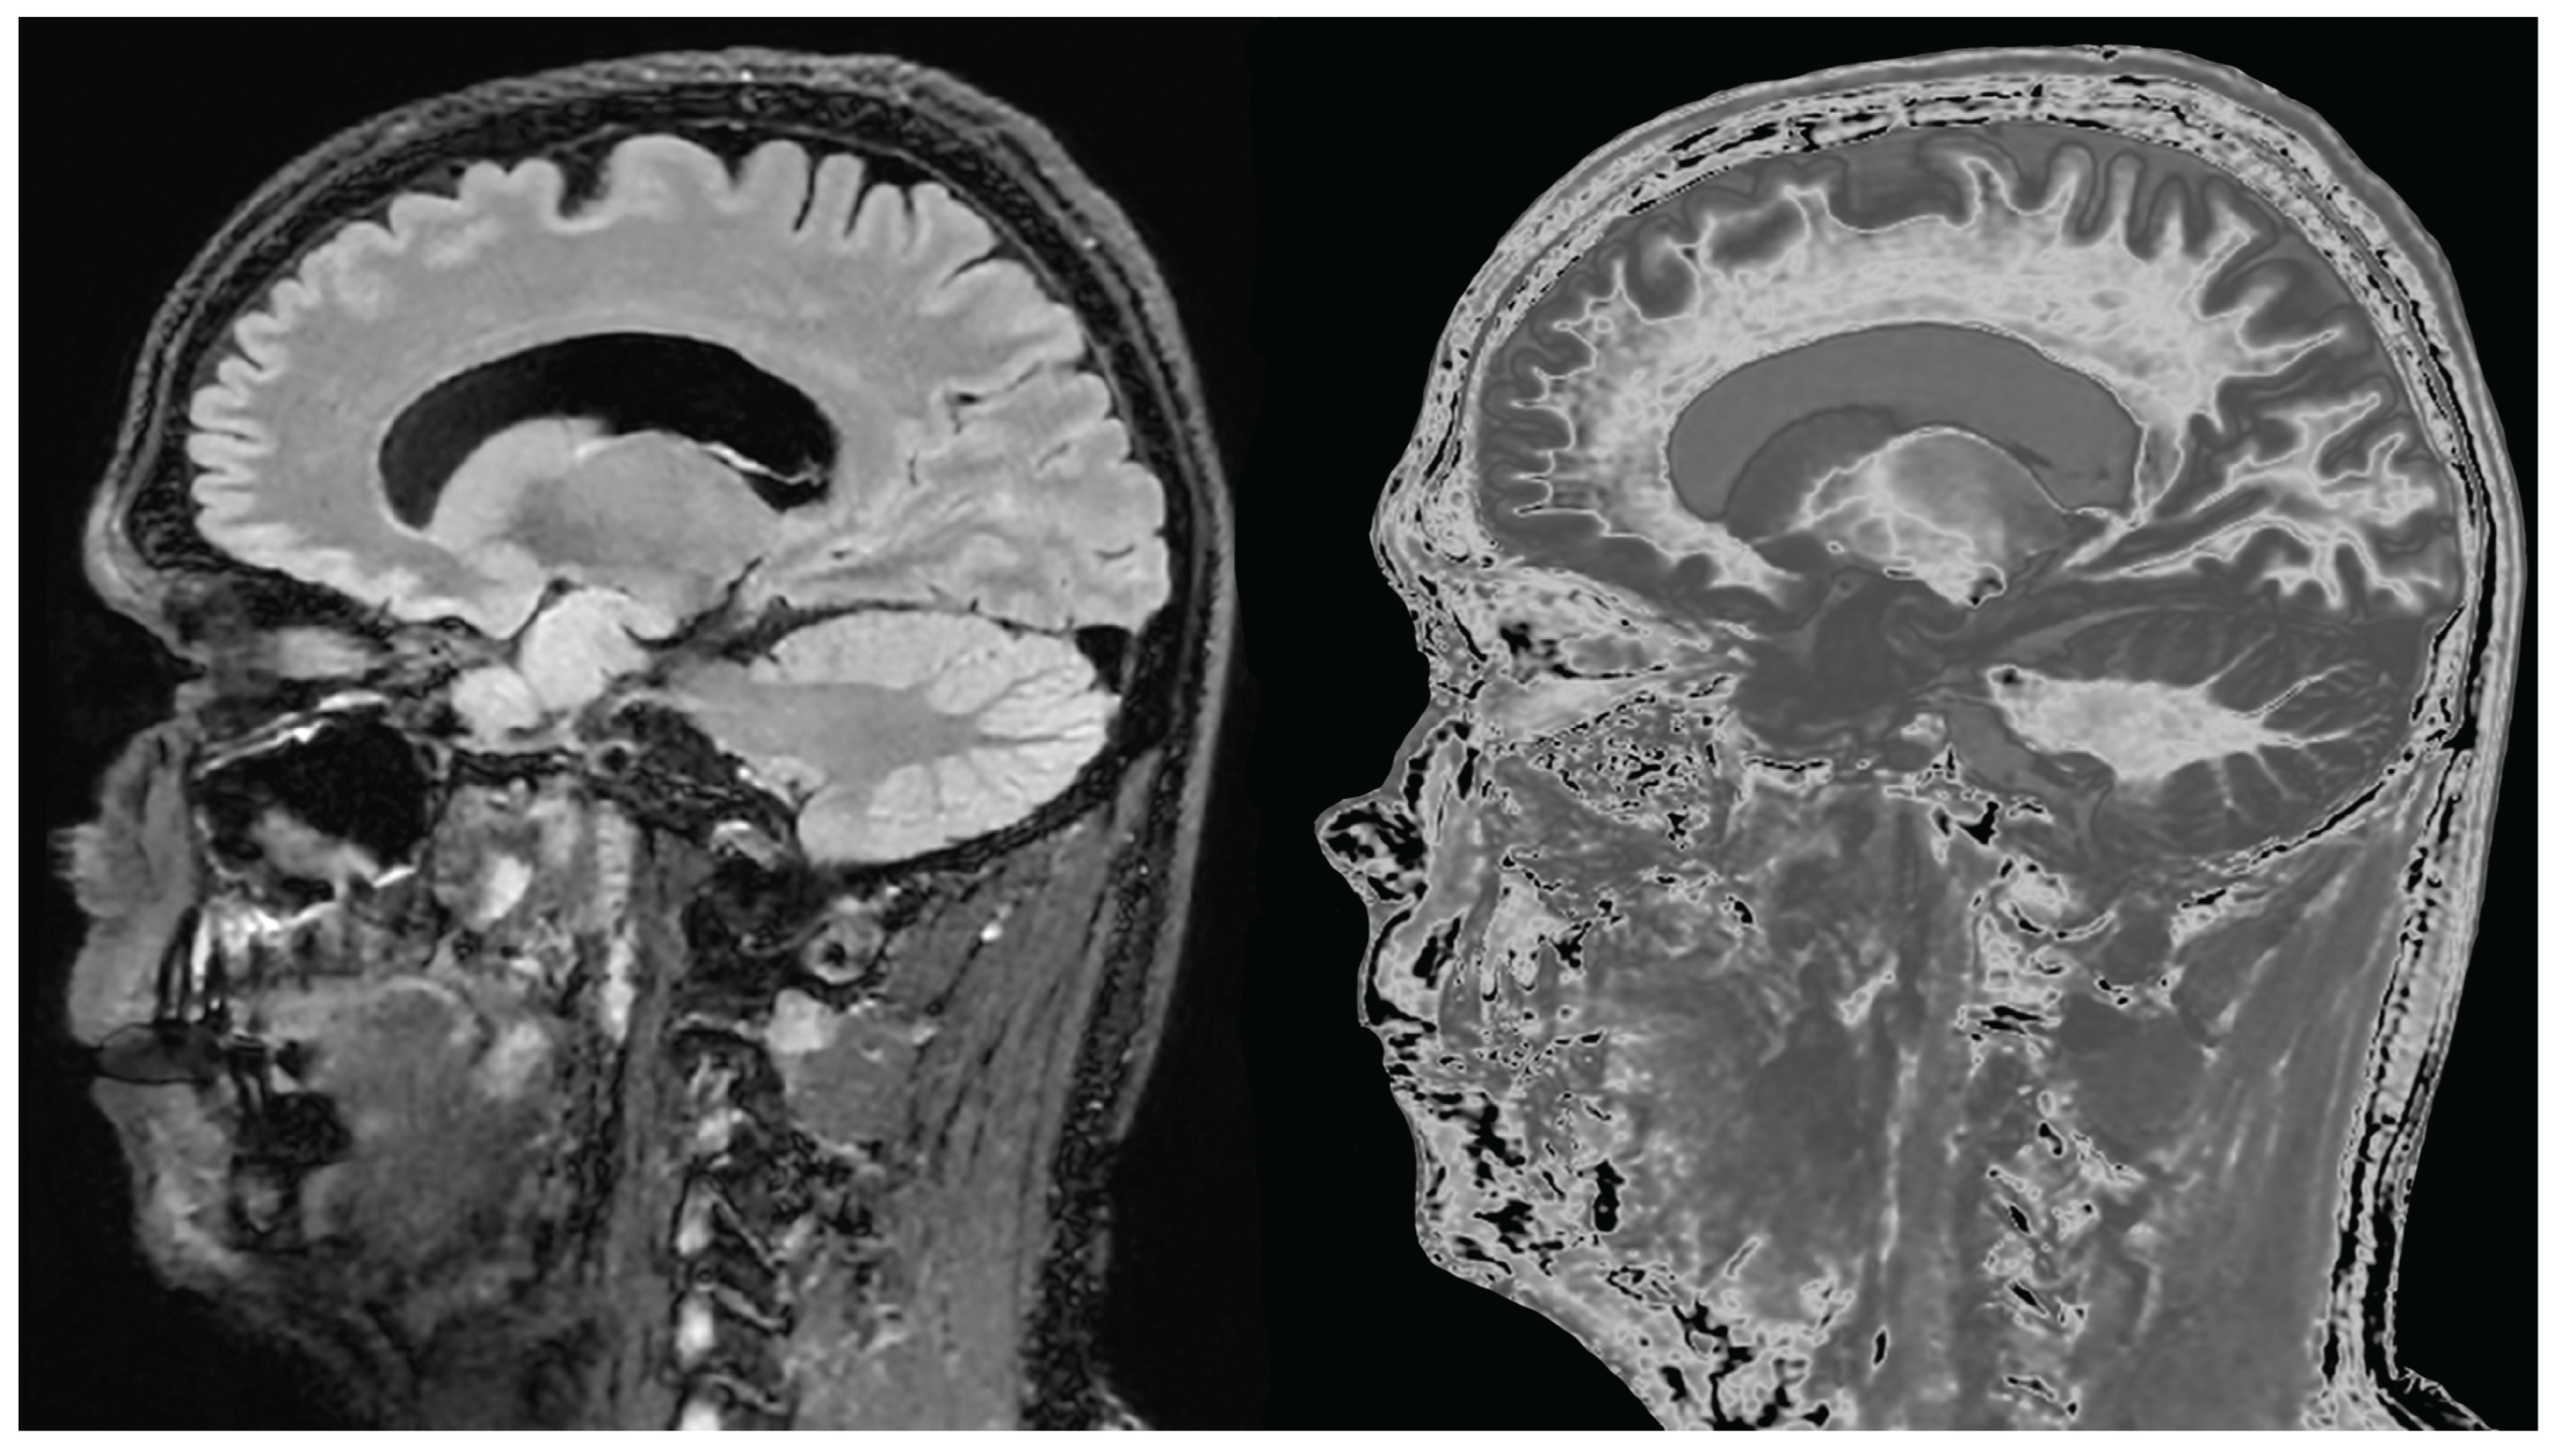

Figure 21.

65-year-old female with a glioma (not shown) post chemotherapy. Parasagittal T2-FLAIR (A) and synthetic narrow mD dSIR (B) images. On the T2-FLAIR image no abnormality is seen. On the dSIR image (B), the white matter has a high signal corresponding to a high grade whiteout sign. This includes the cerebellar white matter which is similar in intensity to the cerebral white matter. There is some sparing of the peripheral white matter in (B).